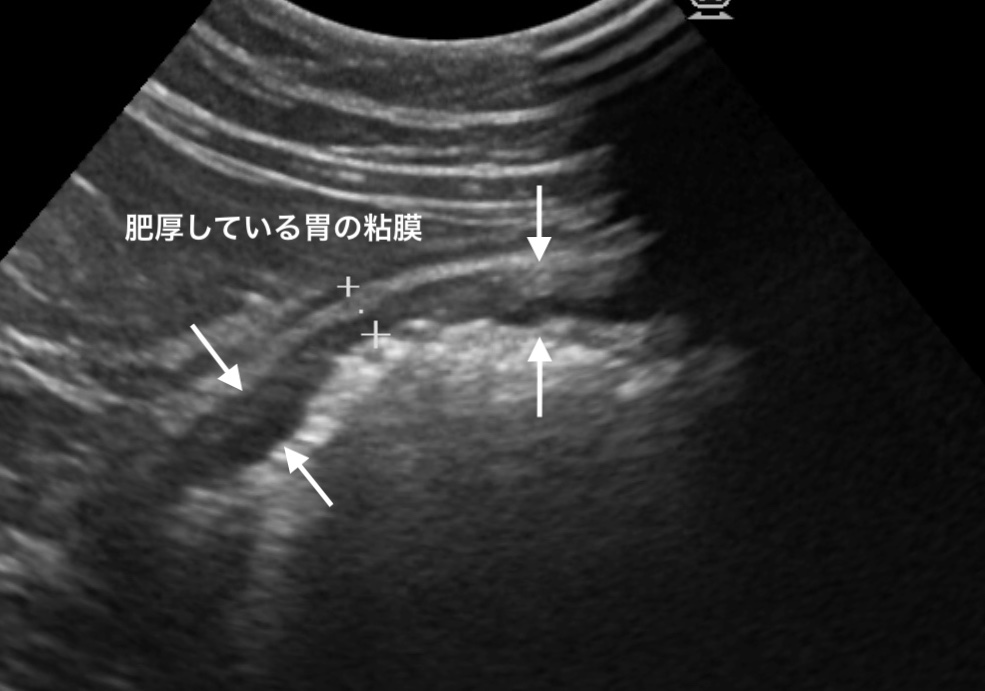

胃の粘膜が肥厚し、一部にポリープ状のものが認められました。